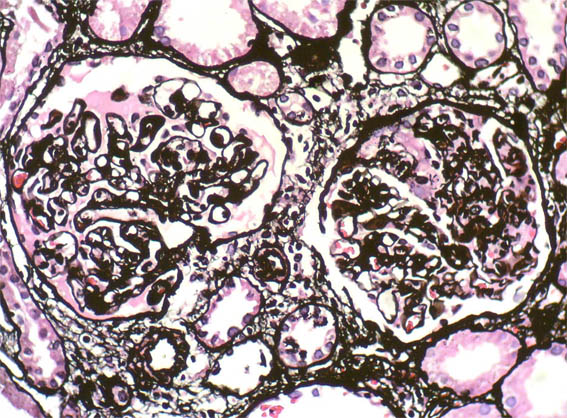

Figure 8. Methenamine-silver stain, X200.